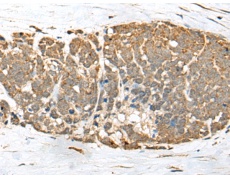

IHC positive control:

Human thyroid cancer

IHC Recommend dilution:

25-100